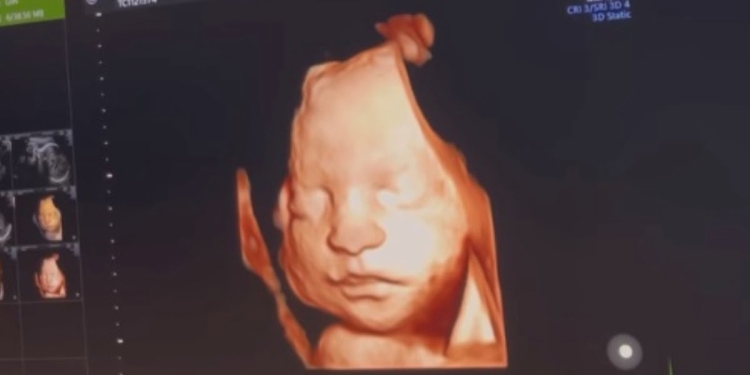

Georgette Polizzi ha pubblicato il video dell’ecografia della figlia. L’ex concorrente di Temptation Island e il marito Davide Tresse aspettano una bambina che si chiamerà Sole e che nascerà a marzo. Georgette non trattiene l’emozione e, a corredo del video, scrive: “Ieri sera sono riuscita a vederla con l’ecografia 3D durante la visita e con la voce rotta dall’emozione non riuscivo a smettere di dire quanto è bella! Sole fortunatamente sta benissimo, cresce a vista d’occhio e ieri ci ha pure fatto un sorriso! È incredibile pensare che tra poche settimane sarà tra le nostre braccia, potremo finalmente toccare il nostro sogno”.

Georgette ha aggiunto che il primo dettaglio che non è passato inosservato sono state le labbra della piccola e ha rivelato: “Ho passato tutta la serata di ieri a studiarla, a guardare e riguardare video e foto dell’ecografia scoprendo ogni volta un dettaglio nuovo del suo visino. La prima cosa che ho notato sono state le sue labbra! Pensavo le avesse prese da me… e invece ha il becchetto del Momo! Le stesse labbra che per anni ho amato alla follia…e che ora ha anche la nostra bambina! Guardate il momo da piccolo quanto le somiglia. Che spettacolo la vita”. Nel video, si sente in sottofondo Georgette Polizzi che commenta le immagini che appaiono sullo schermo: “È tutta mio marito”. Infatti, Georgette ha poi aggiunto delle foto che ritraggono il marito, a dimostrazione che la somiglianza con la figlia che deve nascere è davvero incredibile.